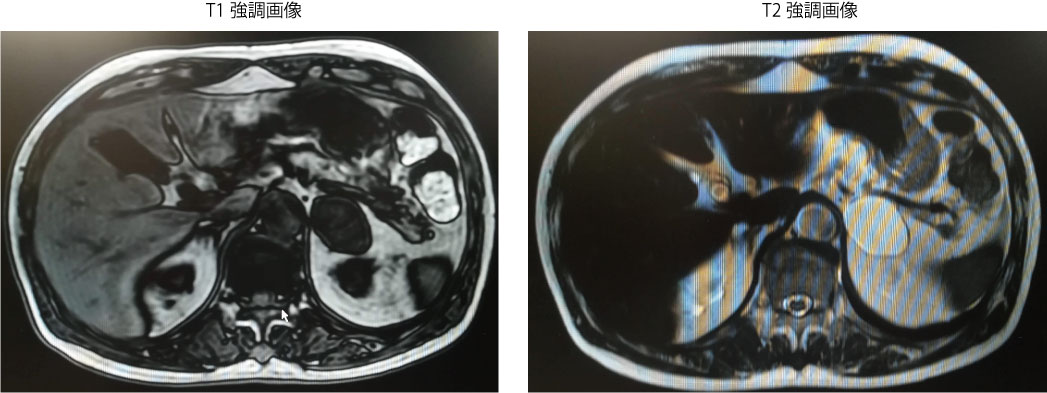

・腹部MRI:副腎嚢胞疑い